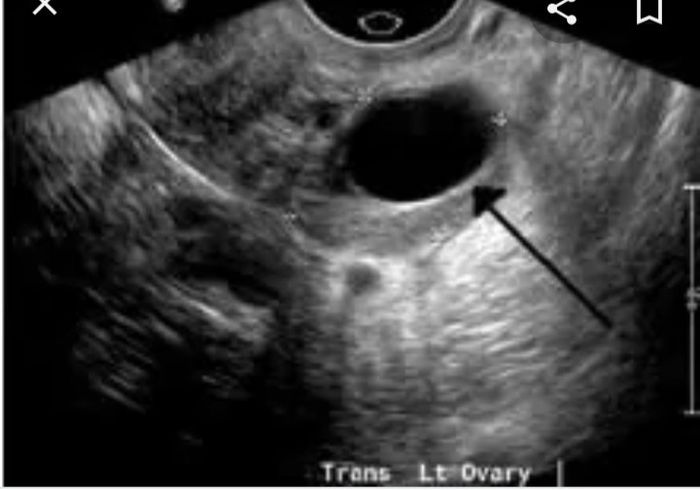

Ti mando la mia ecografia l ultima che hi fatto. Vedi secondo te

Invece questo mi ha detto e un follicolo che sta per scoppiare. Ma non sembra uguale?

Uguale a questo?

Si una palla scura che, per quanto riguarda me, copre quasi tutto l'ovaio.